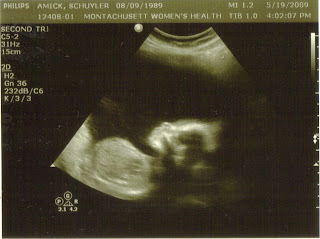

Did you know that on this day last year was Amber's last ultrasound. They did this ultrasound because my bump wasn't measuring the right size. This is when we found out she had stopped growing at some point and was developmentally a 34 week old baby instead of a 37 weeker. We had a faint idea (maybe a little before then) that something wasn't right with Amber. She never was a big kicker. By the way these pictures are from Amber's 20 week ultrasound when they made sure her anatomy was all right. During that ultrasound Amber never once opened her left hand, the one she never opened until she got splints at five months.

Her profile at 20 weeks and at birth. Pretty cool!